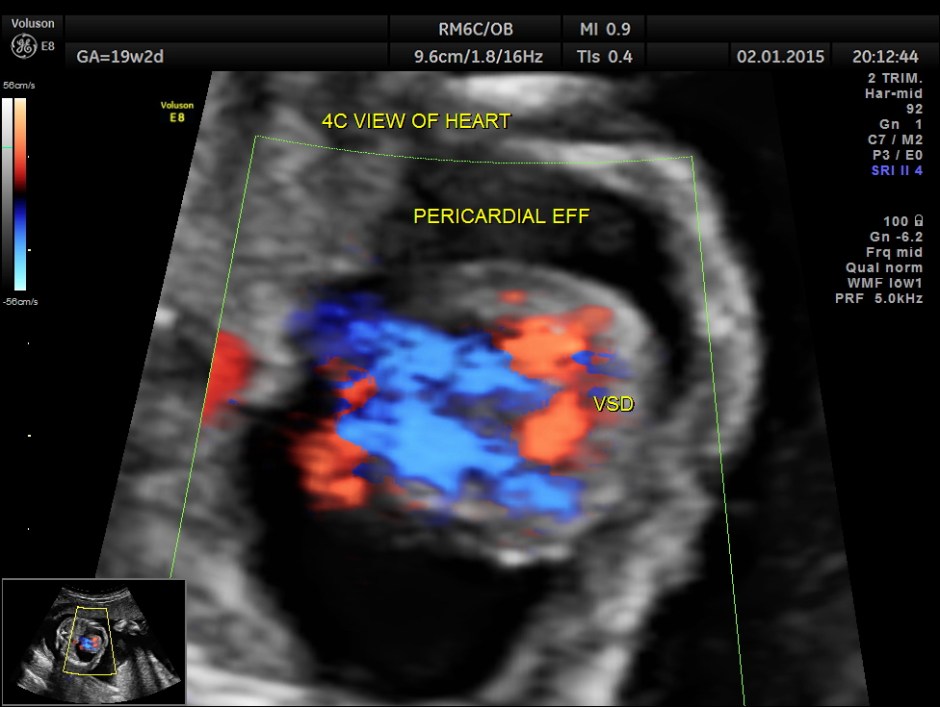

A large pericardial effusion is seen.

A prominent muscular ventricular septal defect is seen.

This fetus had a large pericardial effusion with structural defect of the heart – VSD and disproportionately smaller left heart – possibly co-arctation of aorta . The patient was advised chromosomal studies and was lost for follow up.